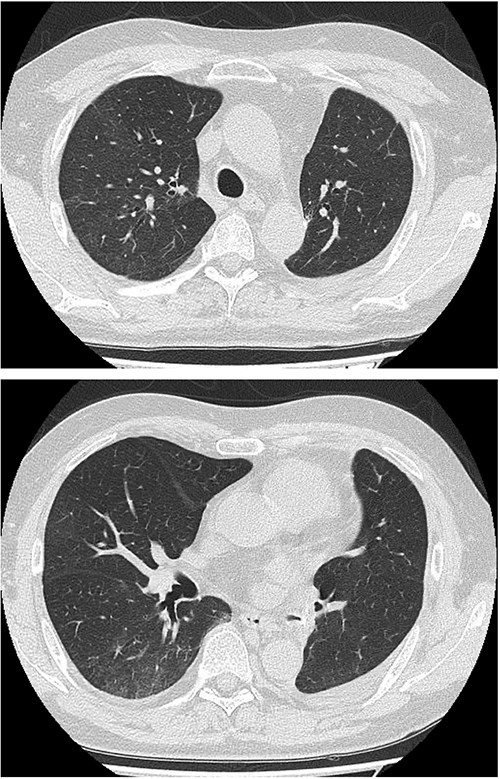

Methylprednisolone pulse therapy (1 g/day for 3 days) was initially administered, followed by oral prednisolone (30 mg). However, oxygen requirements increased to 4 L on POD 31 (Fig. 3). On POD 36, a second methylprednisolone pulse course was initiated with cyclosporine A (150 mg) owing to progressive consolidation on chest imaging (Fig. 2d). Oxygen support was discontinued by POD 38, and he was discharged on POD 52. Follow-up image on POD 104 showed substantial radiological improvement (Fig. 4). Immunosuppressive medications were successfully tapered and discontinued by POD 329. This case was diagnosed as delayed-onset OP as a manifestation of post-acute COVID-19 syndrome, characterized by the biphasic clinical course and distinctive radiological progression occurring weeks after acute COVID-19 infection.

Follow-up chest imaging on postoperative Day 104 showing significant resolution of bilateral consolidations observed during the acute phase of organizing pneumonia.